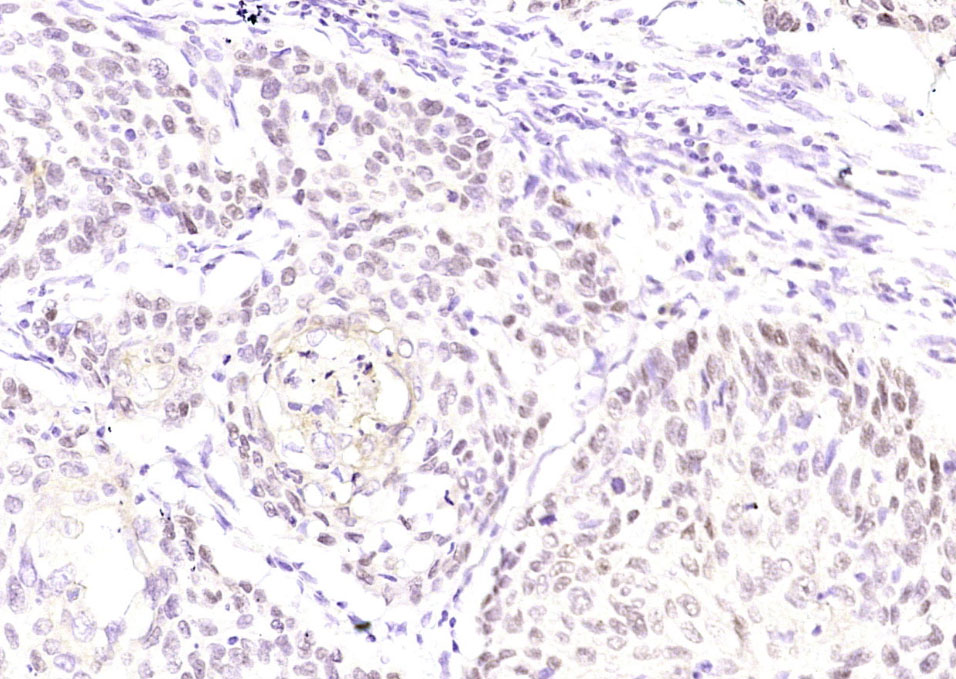

| 英文名称 | P63(ready to use) Mouse mAb |

| 中文名称 | 肿瘤抑制基因P63单克隆抗体(工作液) |

| 产品应用 | WB, IHC-P, IHC-F, ICC/IF, IF Not yet tested in other applications. |

| 交叉反应 | Human |